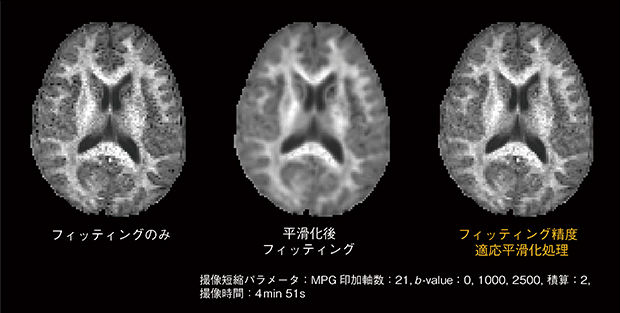

さらに,画質劣化を抑制するために,画像処理アルゴリズムの開発を進めています4)。フィッティング精度が不足する場合,画像に粒子状の暗点(ペッパーノイズ)が多く発生します(図5)。また,単純に各拡散強調画像を平滑化処理した後にフィッティングする方法では,ペッパーノイズは抑制できますが,空間分解能が低下してしまいます。これを防ぐために,フィッティング精度が不足している画素のみを平滑化処理するフィッティング精度適応平滑化処理技術を開発しています。本技術により空間分解能を大きく低下させることなく,ペッパーノイズを低減可能なことを確認しています。

図5 フィッティング精度適応平滑化処理によるDKI(MK)の画質向上

フィッティングのみで多発しているペッパーノイズと平滑化後フィッティングで生じている空間分解能低下が,開発しているフィッティング精度適応平滑化処理では共に軽減しています。1.5T MRIでは,約5分の計測時間で良好な画質が得られています。